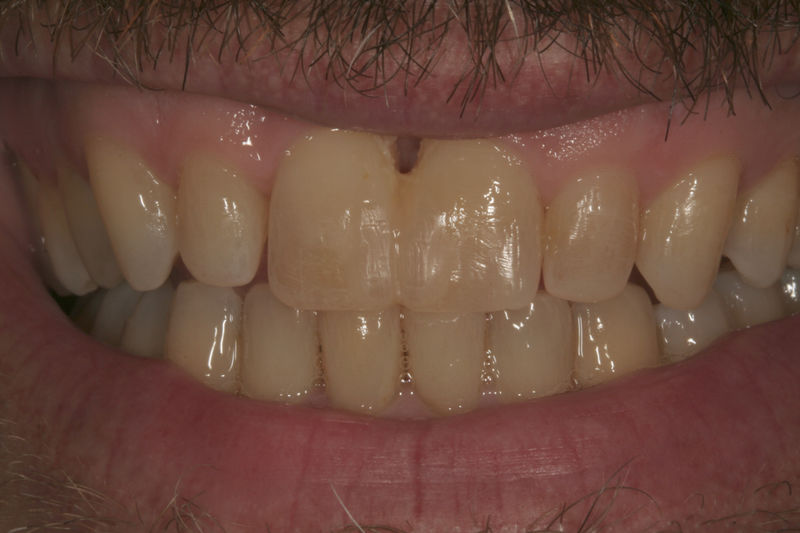

Amplia gama de tratamientos para mejorar la apariencia de la sonrisa, corrigiendo el color, la forma, el tamaño, la alineación y la posición de los dientes. Los procedimientos más comunes y solicitados incluyen el blanqueamiento dental, las carillas y coronas, así como las resinas.

Son restauraciones que cubren toda la cara frontal del diente, generalmente empleadas en el sector anterior y cuya finalidad es primariamente estética.

Restauraciones fabricadas en el laboratorio con materiales estéticos, los cuales cubren de manera total dientes anteriores y posteriores. Se utilizan primariamente para restaurar dientes con caries, fracturas y/o defectos amplios, así como soportes de puentes. Para poder enviar el caso al laboratorio se toman impresiones utilizando materiales de impresión o técnicas modernas digitales.